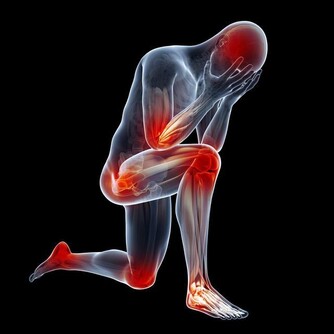

*****十、壓力和焦慮*****

對任何壓力處境都保持良好的心態、合理安排時間和自己所能、學會放鬆(如瑜伽、冥想、體育鍛煉或深呼吸)都會起到幫助作用。

一種快速鎮靜方法是擠壓食指和拇指之間的多肉部位30秒鐘,中醫認為這種方法能緩解上半身的壓力和張力。